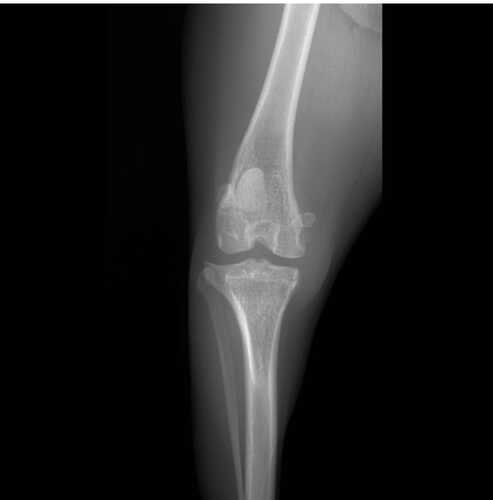

A Cindy tem 1 ano e 8 meses, é muito brincalhona e agitada. Sua brincadeira favorita é correr e pular alto. Um certo dia em uma de suas brincadeiras, a Cindy pulou e escorregou, o que acabou levando a uma ruptura do ligamento cruzado, fazendo ela ter dor e apoiar a pata no chão com dificuldade.